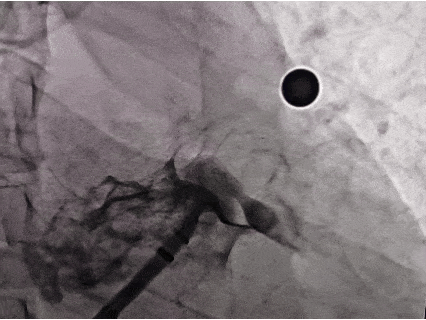

封堵器释放后评估

符合PASS释放原则,释放封堵器

释放后造影,无残余分流

释放后封堵器形态良好,封堵完全